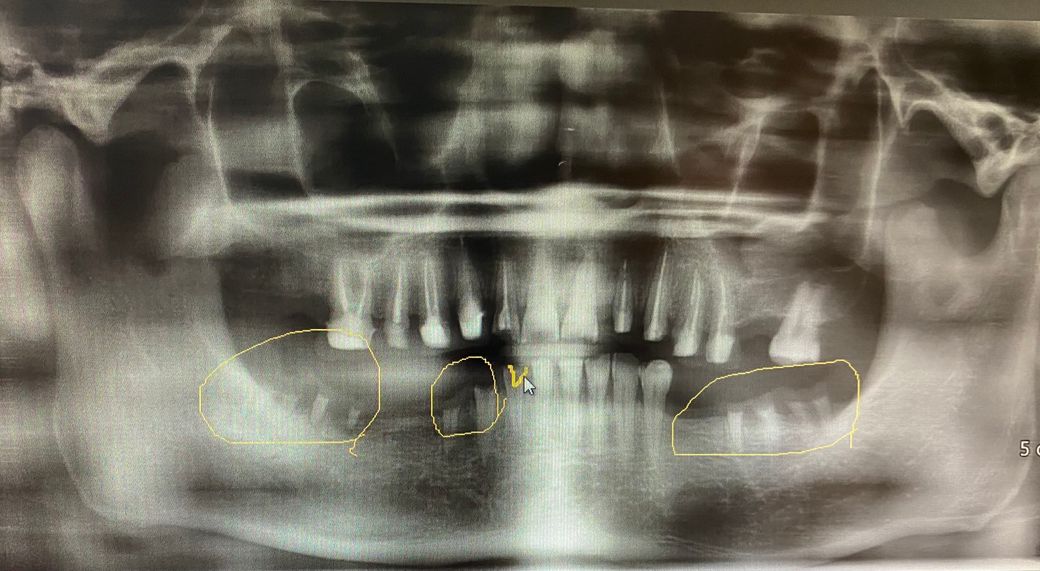

저는 30초반에 임플란트를 대략 8-9개 정도 식립해야할 상황입니다 크라운은16개 진행예정이구요

현재 하악에 남아있는 치아는 앞니6개 정도만 남아있고

어금니는 하나도없는데 제가 다니는 치과는 네비게이션임플란트를 진행하지 않고있습니다

이번에 앞니 신경치료를했는데 파노라마찍어보니 약제가 치아 밖으로 나올정도로 넣어놓으셨던데 믿어도 되는걸까요??